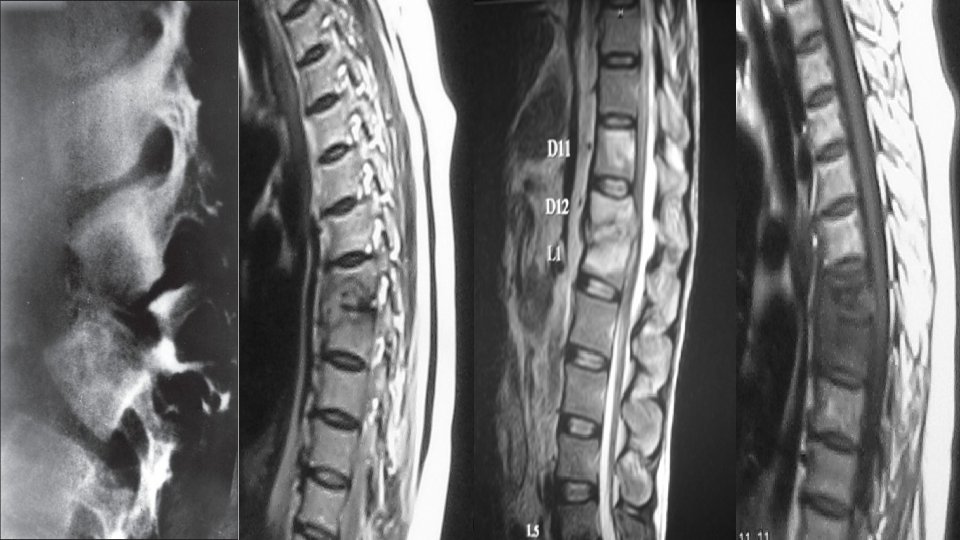

V. Обяснение на дегенерациите V. Explanation of degenerations